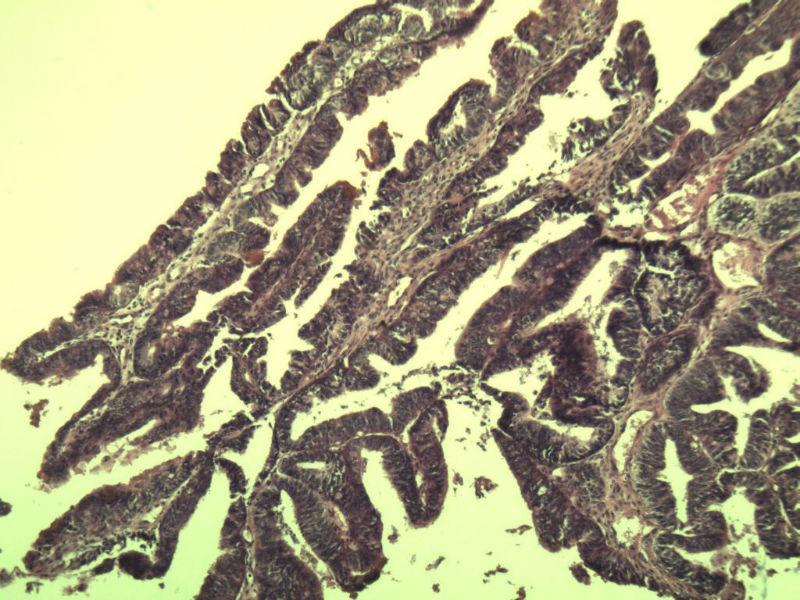

女 32岁 不规则阴道流血 一年  请各位老师看看 谢谢了

遵义医学院附属医院会诊结果    "复杂性增生伴非典型性 "

补充一下病史 病人10个月前因月经不规则行诊刮 诊断非典型性增生  上了曼月乐避孕环(好像是缓慢释放孕激素的那种),         都用激素治疗大半年了 还是这个样子 我还是觉得是癌  只有追踪一下以后病人的情况吧

高分化子宫内膜样癌

非典型复杂性子宫内膜增生,应了解雌孕激素情况。

非典型复杂性子宫内膜增生,32岁,太年轻了,是不是要考虑她的激素情况?

子宫内膜复杂性非典型性增生,局灶区间质肉芽样(图5)及蜕膜样变,不够癌,建议临床查激素水平并追踪。

从照片看,没看到浸润的地方,我考虑是子宫内膜重度不典型增生。

既“局灶区间质肉芽样(图5)及蜕膜样变”,为何不能报“局灶呈高分化子宫内膜样腺癌改变”?个人理解,报告中所含的“局灶×××”,应该是更高级别的但范围较小或较局限的病变。